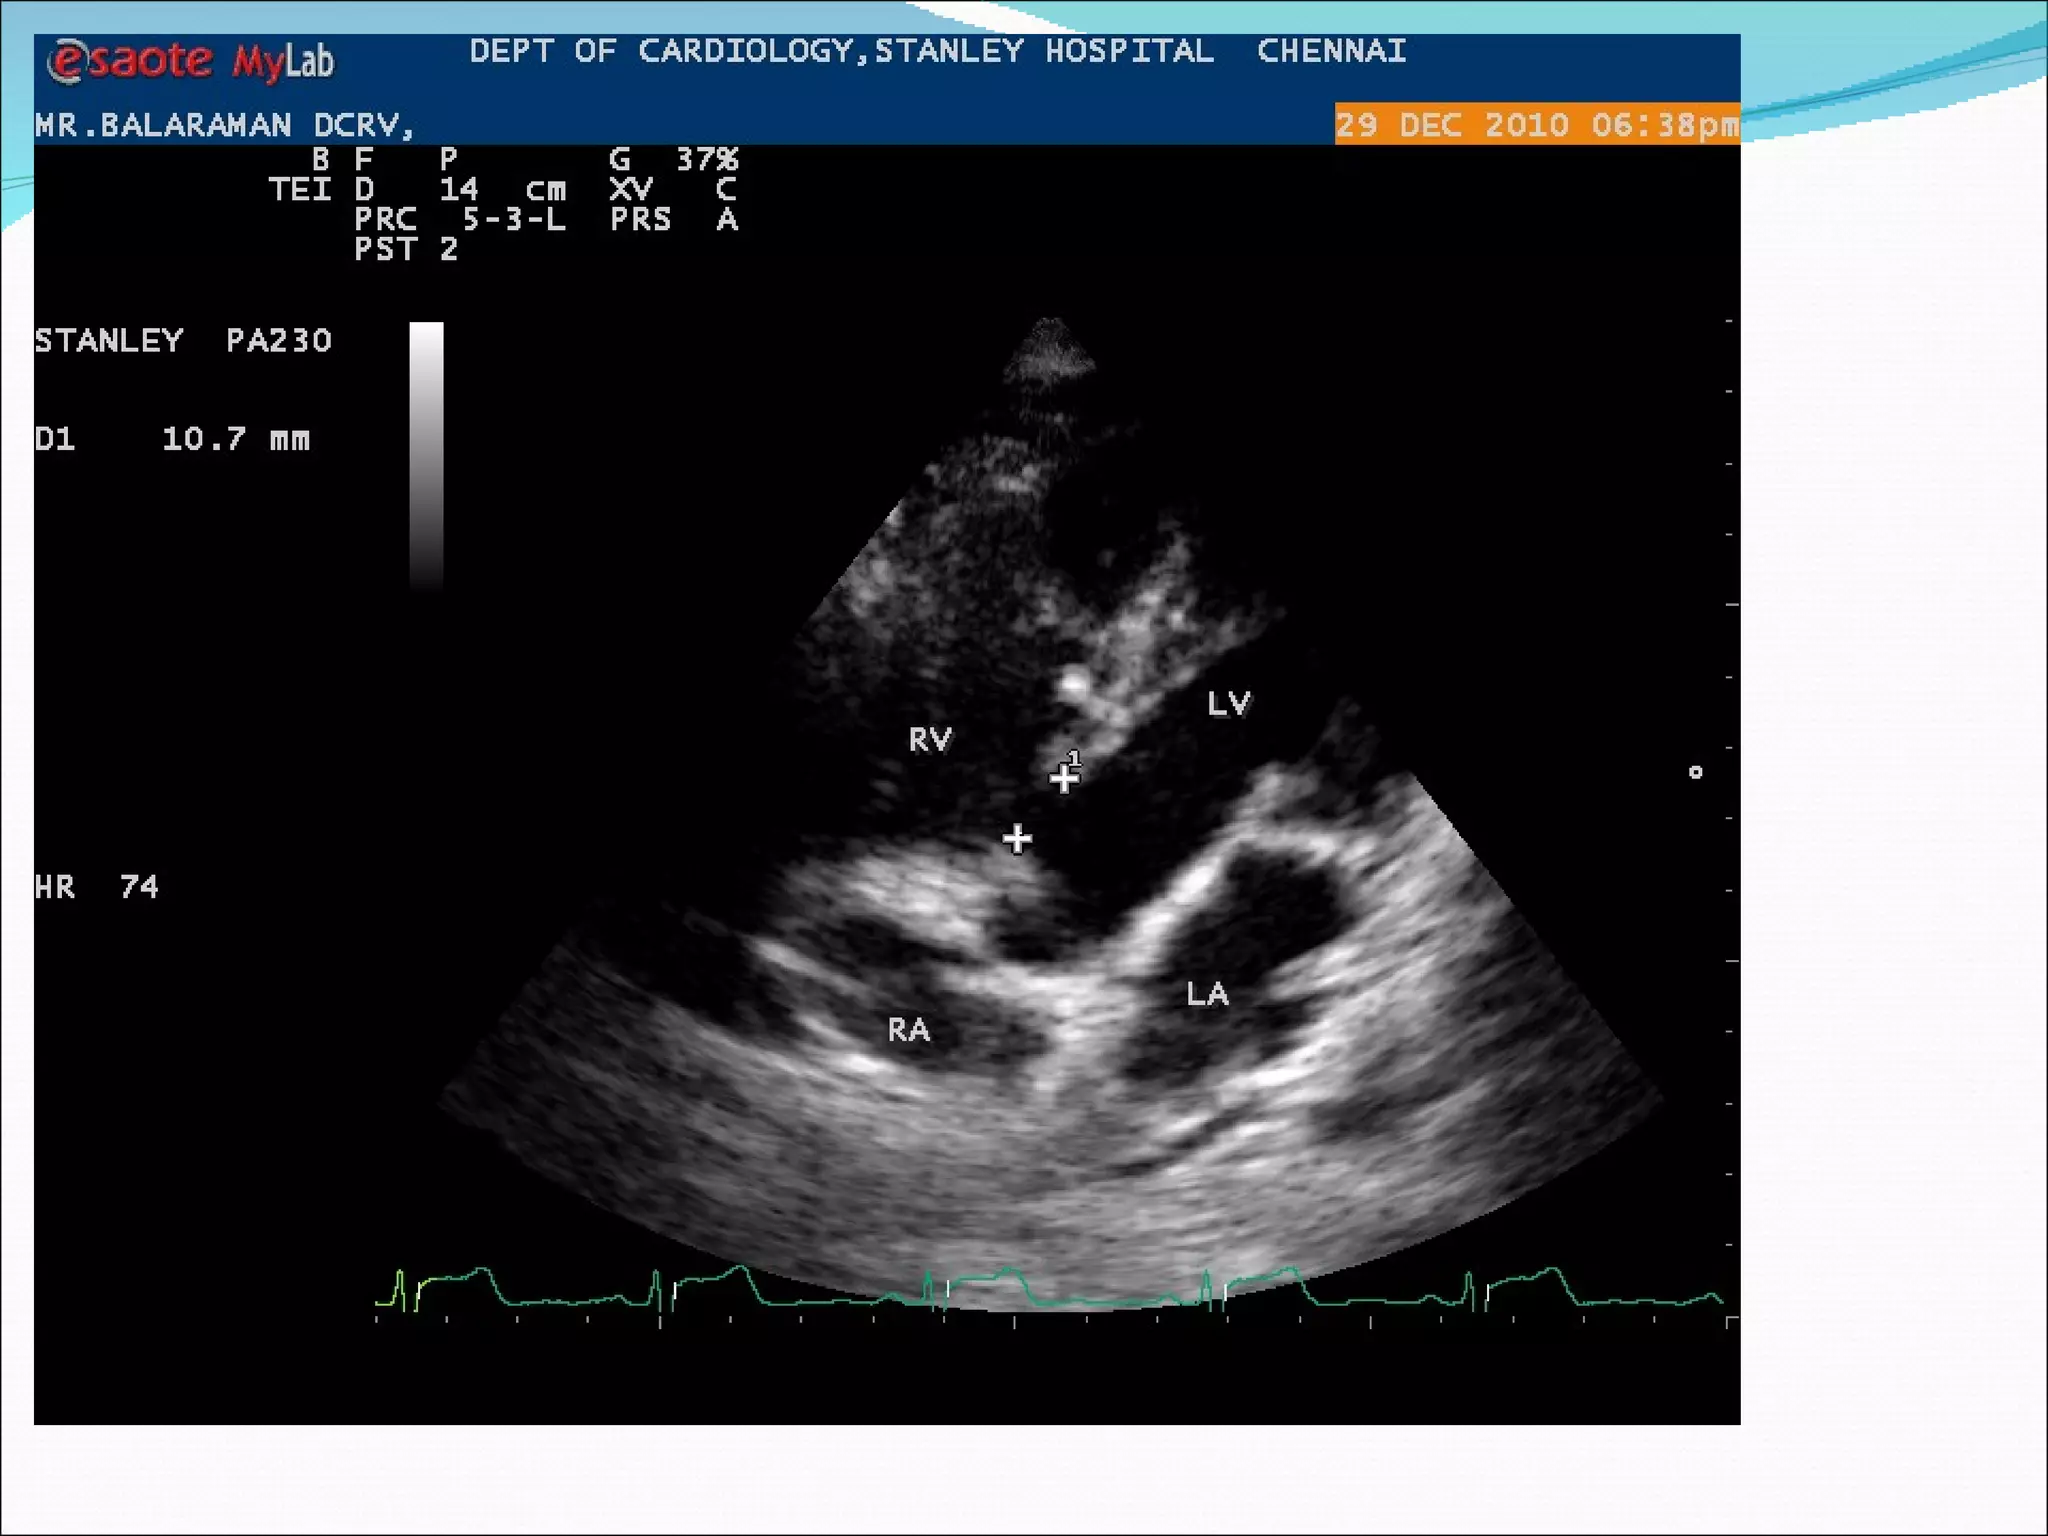

A 20-year-old male patient presented with complaints of palpitations and exertional breathlessness. On examination, he had a heart rate of 64 beats per minute, blood pressure of 100/70 mmHg, and a grade 5/6 pansystolic murmur heard best over the left parasternal area. An ECG showed right ventricular hypertrophy and right axis deviation. An echocardiogram confirmed the diagnoses of a ventricular septal defect and double chambered right ventricle.